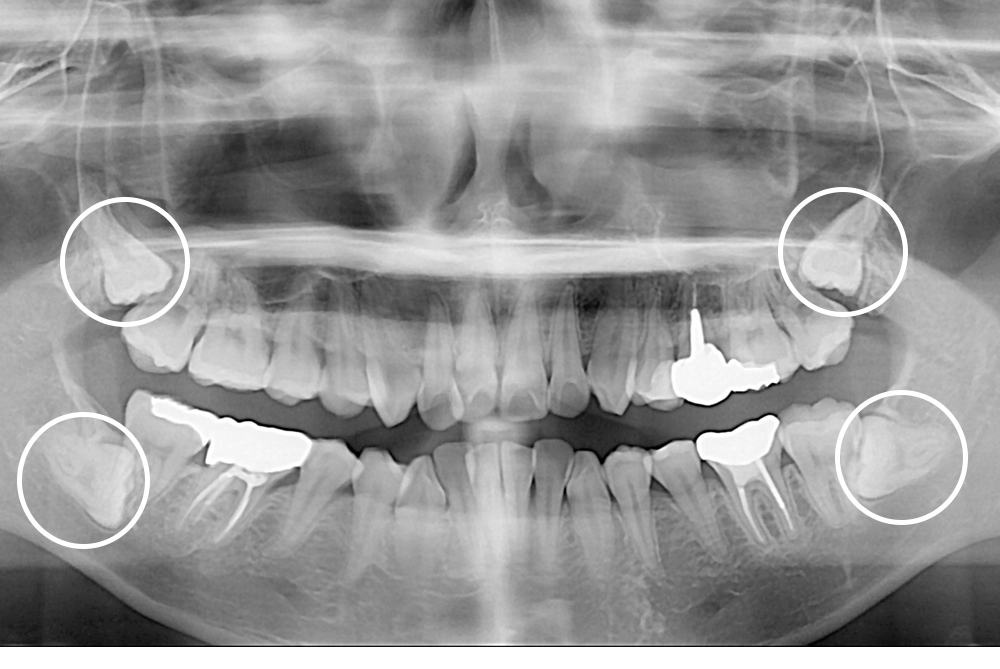

[사랑니] 매복 사랑니 발치

치료전 : 2021-04-08

세종치과는 구강악안면외과학 박사이신 원장님이 발치하는 치과입니다.